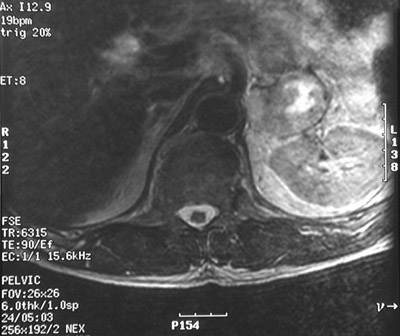

Here is an abdominal T2 weighed MRI scan that shows a left adrenal pheochromocytoma with bright central necrosis.